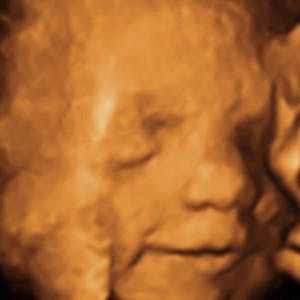

Gravid

Vi gør en dyd ud af at klæde dig godt på både før, under og efter din graviditet. Vi ved, at der kan komme mange spørgsmål til din graviditet, fødsel, amning, din babys udvikling og mange flere emner, derfor har vi samlet guides, tips & tricks samt læsernes egne fortællinger i dette gravid univers.